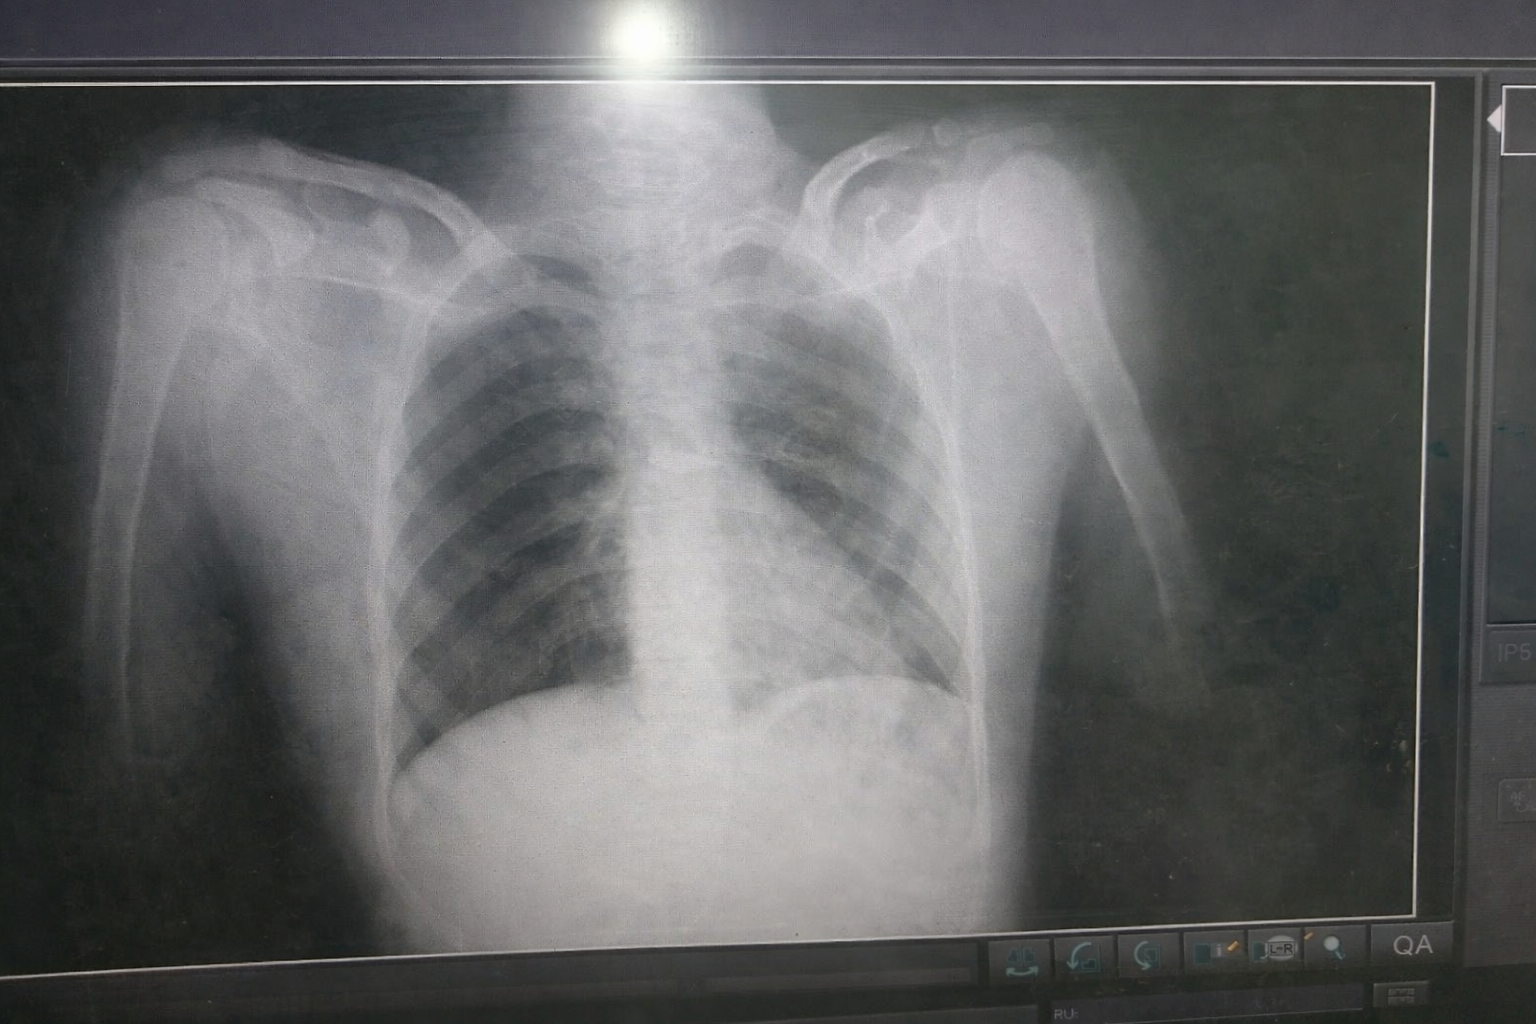

فجأة، دوّت أصوات القذائف الإسرائيلية في محيط المكان، وترافق مع ذلك إطلاق نار كثيف وتحليق طائرات "الكواد كابتر"، في ثوانٍ قليلة تحولت أروقة المستشفى ومحيطها إلى مشهد من الفوضى والخوف، ووسط ذلك كله، أصيب إبراهيم بطلق ناري استقر في ظهره، تحديدًا عند الفقرة السادسة.

كانت تلك الكلمات بداية الصدمة الحقيقية. فالإصابة التي تعرض لها إبراهيم تسببت في ضرر خطير في الحبل الشوكي، ما أدى إلى فقدانه الإحساس في الجزء السفلي من جسده.

ورغم خطورة الحالة، لم يتمكن الأطباء من إجراء عملية جراحية له، وتشرح والدته السبب قائلة: "فبسبب قلة الإمكانيات والمعدات الطبية وعدم توفر العلاج المناسب، لم تُجرَ له أي عملية، كان الأطباء يخشون أن يؤدي التدخل الجراحي في هذه الظروف إلى قطع الحبل الشوكي بالكامل".